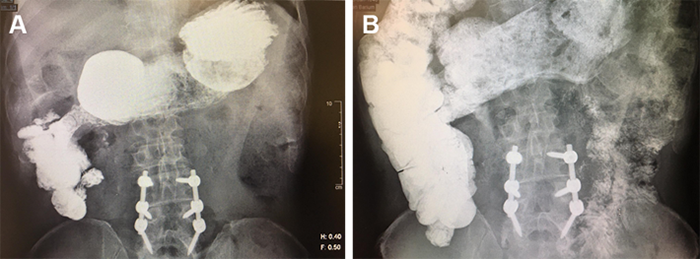

The patient developed bilious emesis postoperatively due to gastroparesis of an unclear etiology, requiring intermittent nasogastric decompression. Contrast studies were negative for leak or obstruction. A gastrojejunostomy tube was placed for gastric drainage and distal feeding; there was initial difficulty tolerating jejunal feeds. Further contrast studies showed contrast passing through the entire bowel, with retrograde reflux into the stomach, even when administered through the jejunal port.

Figure 2. Contrast study via jejunal port revealing reflux of contrast into stomach. Published with Permission

As noted previously, the patient had oropharyngeal dysphagia due to unilateral vocal cord paralysis from a suspected prior iatrogenic intubation injury. Because of the persistent biliary reflux combined with inadvertent aspiration risk, we undertook expeditious correction. The patient was taken back for the creation of a Roux-en-Y gastrojejunostomy for reflux prevention. The proximal limb was anastomosed 45 centimeters distal to the gastrojejunostomy to the jejunum.